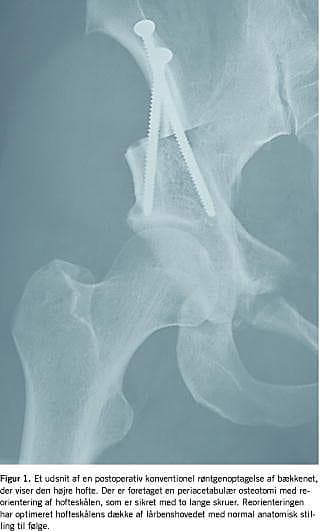

Formålet med den periacetabulære osteotomi er at reorientere hofteskålen, således at dækket af lårbenshovedet optimeres og tilnærmes den normale anatomi [8] (Figur 1). Herved ophæves den uhensigtsmæssige biomekanik, hvilket tænkes at kunne udskyde eller helt eliminere artroseudviklingen i hofteleddet. Ud fra et mekanisk synspunkt udmærker den periacetabulære osteotomi sig ved, at bækkenringen lades intakt samt ved, at dets indre dimensioner ikke ændrer sig. Ved periacetabulær osteotomi udføres der osteotomier i fem trin omkring hofteskålen, som herefter kan mobiliseres og reorienteres i henhold til den præoperative plan [1]. Den fri osteotomerede blok med hofteskålen fikseres oftest med to lange skruer. Tidligere blev indgrebet udført med brug af omfattende kirurgiske adgange, men det kan nu udføres med en minimalt invasiv teknik under vejledning af røntgengennemlysning [9]. De første otte uger efter operationen mobiliseres patienterne med partiel støtte ved hjælp af krykstokke.